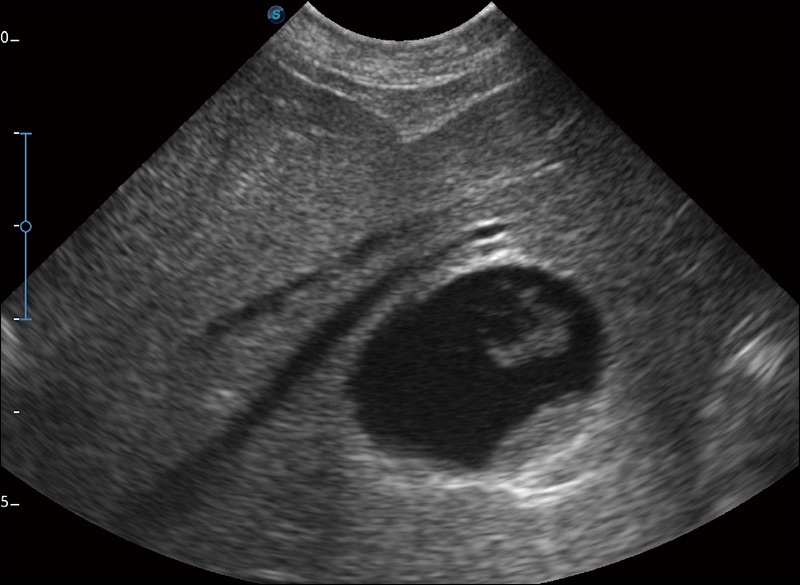

穿刺针增强

高清显示穿刺进针情况

连续波多普勒成像CW

为心脏功能评估提供更多诊断信息